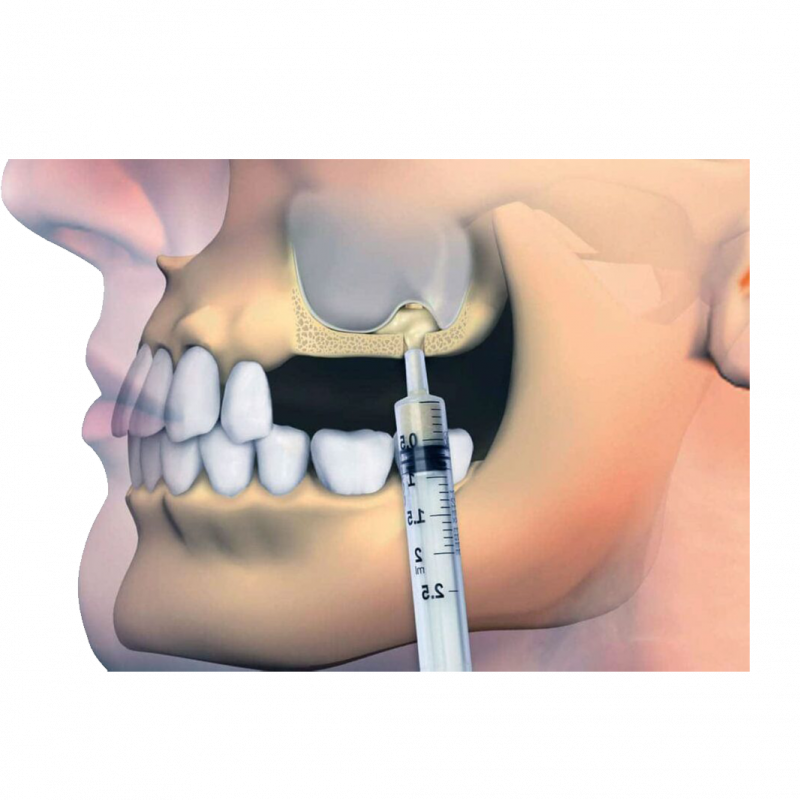

Lokal anestezi uygulandıktan sonra, diş hekimi veya çene cerrahı diş etinde kesi oluşturarak, sinüs membranını (zar) ortaya çıkarmak için çene kemiğinde bir “pencere” açılır. Daha sonra sinüs membranı uygun aletler ile eleve edilir yani yukarı kaldırılır.